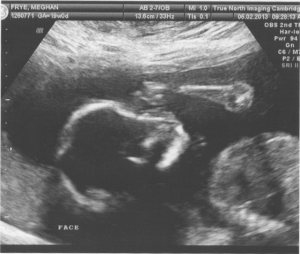

We got our first look at our little French Frye at the True North in Cambridge today. After a very thorough ultrasound, they brought Erik in for our first peek. First she showed us the head and face, little arms and legs. Then the money shot – saw a little bum and oh, what is that little protrusion? All I could squeak out was “is that a little penis?!?!”. Reliving the story later this evening, Erik and I both realized she actuallydidn’t answer… but yeah – it’s a boy!! Erik always said he would be happy either way – but I was ecstatic to learn we are having a boy (I’m sure I would’ve been fine with a girl too, but now I know my baby won’t be wearing pink! Hurray!).